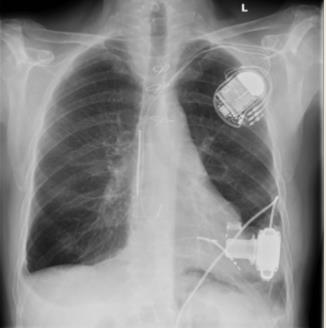

Neue Herzschrittmacher: Kein Kabel, keine Elektroden

„Diese Technologie ist zukunftsweisend“, betonte bei der Herbsttagung der Deutschen Gesellschaft für Kardiologie (DGK) Prof. Dr. Burghard Schumacher…